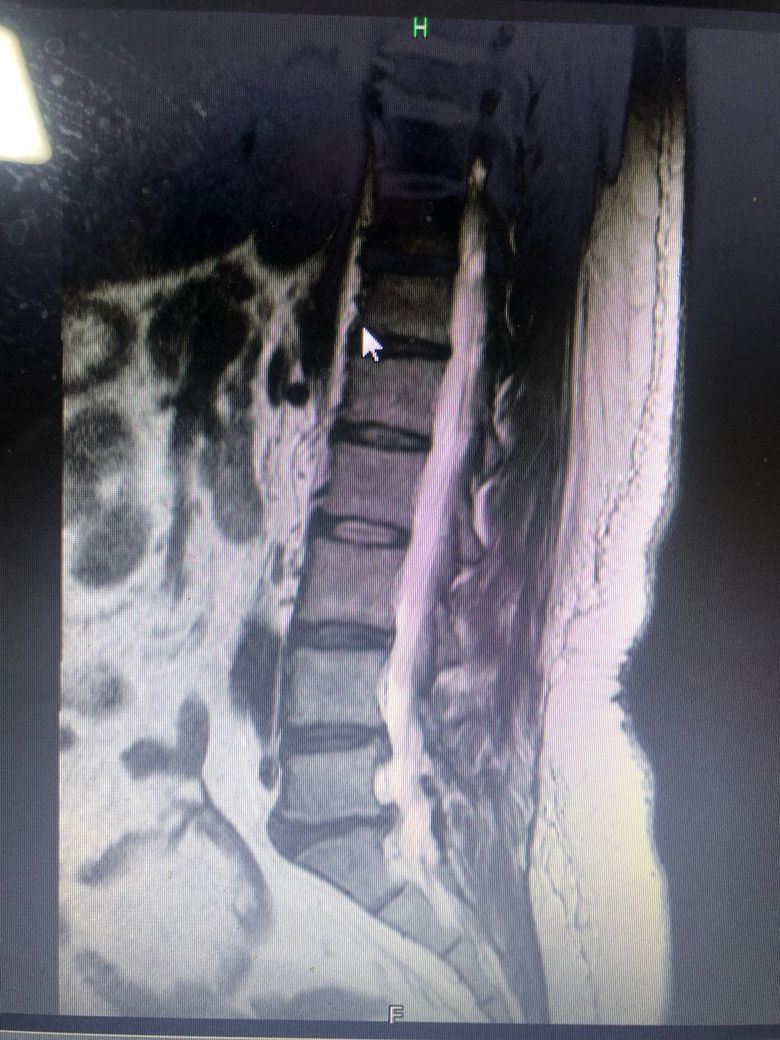

• 1번 째 사진